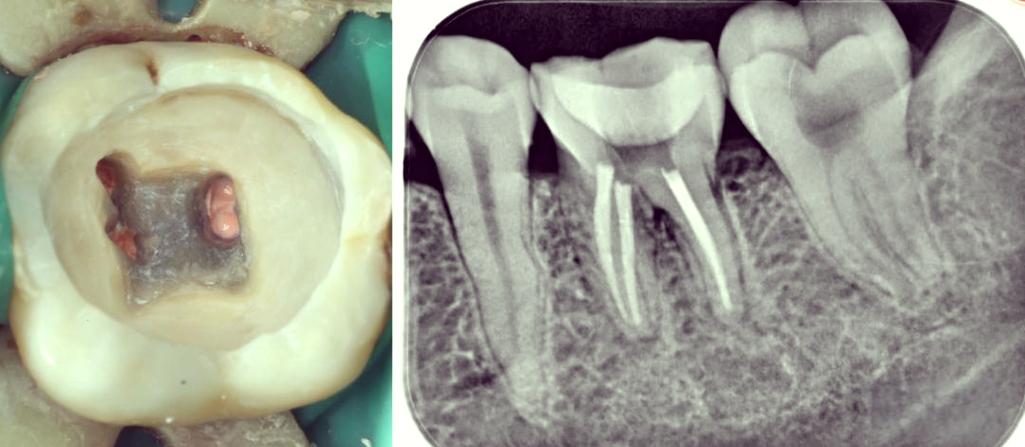

(图片来源网络,侵删)- 确认桩核的形态、高度、位置、表面粗糙度、与牙体组织的密合度均符合要求。

- 影像学评估: 术前必须拍摄根尖片,了解桩核的长度、直径、形态、与根管壁的密合度、根管弯曲度、根尖情况、有无根折等。